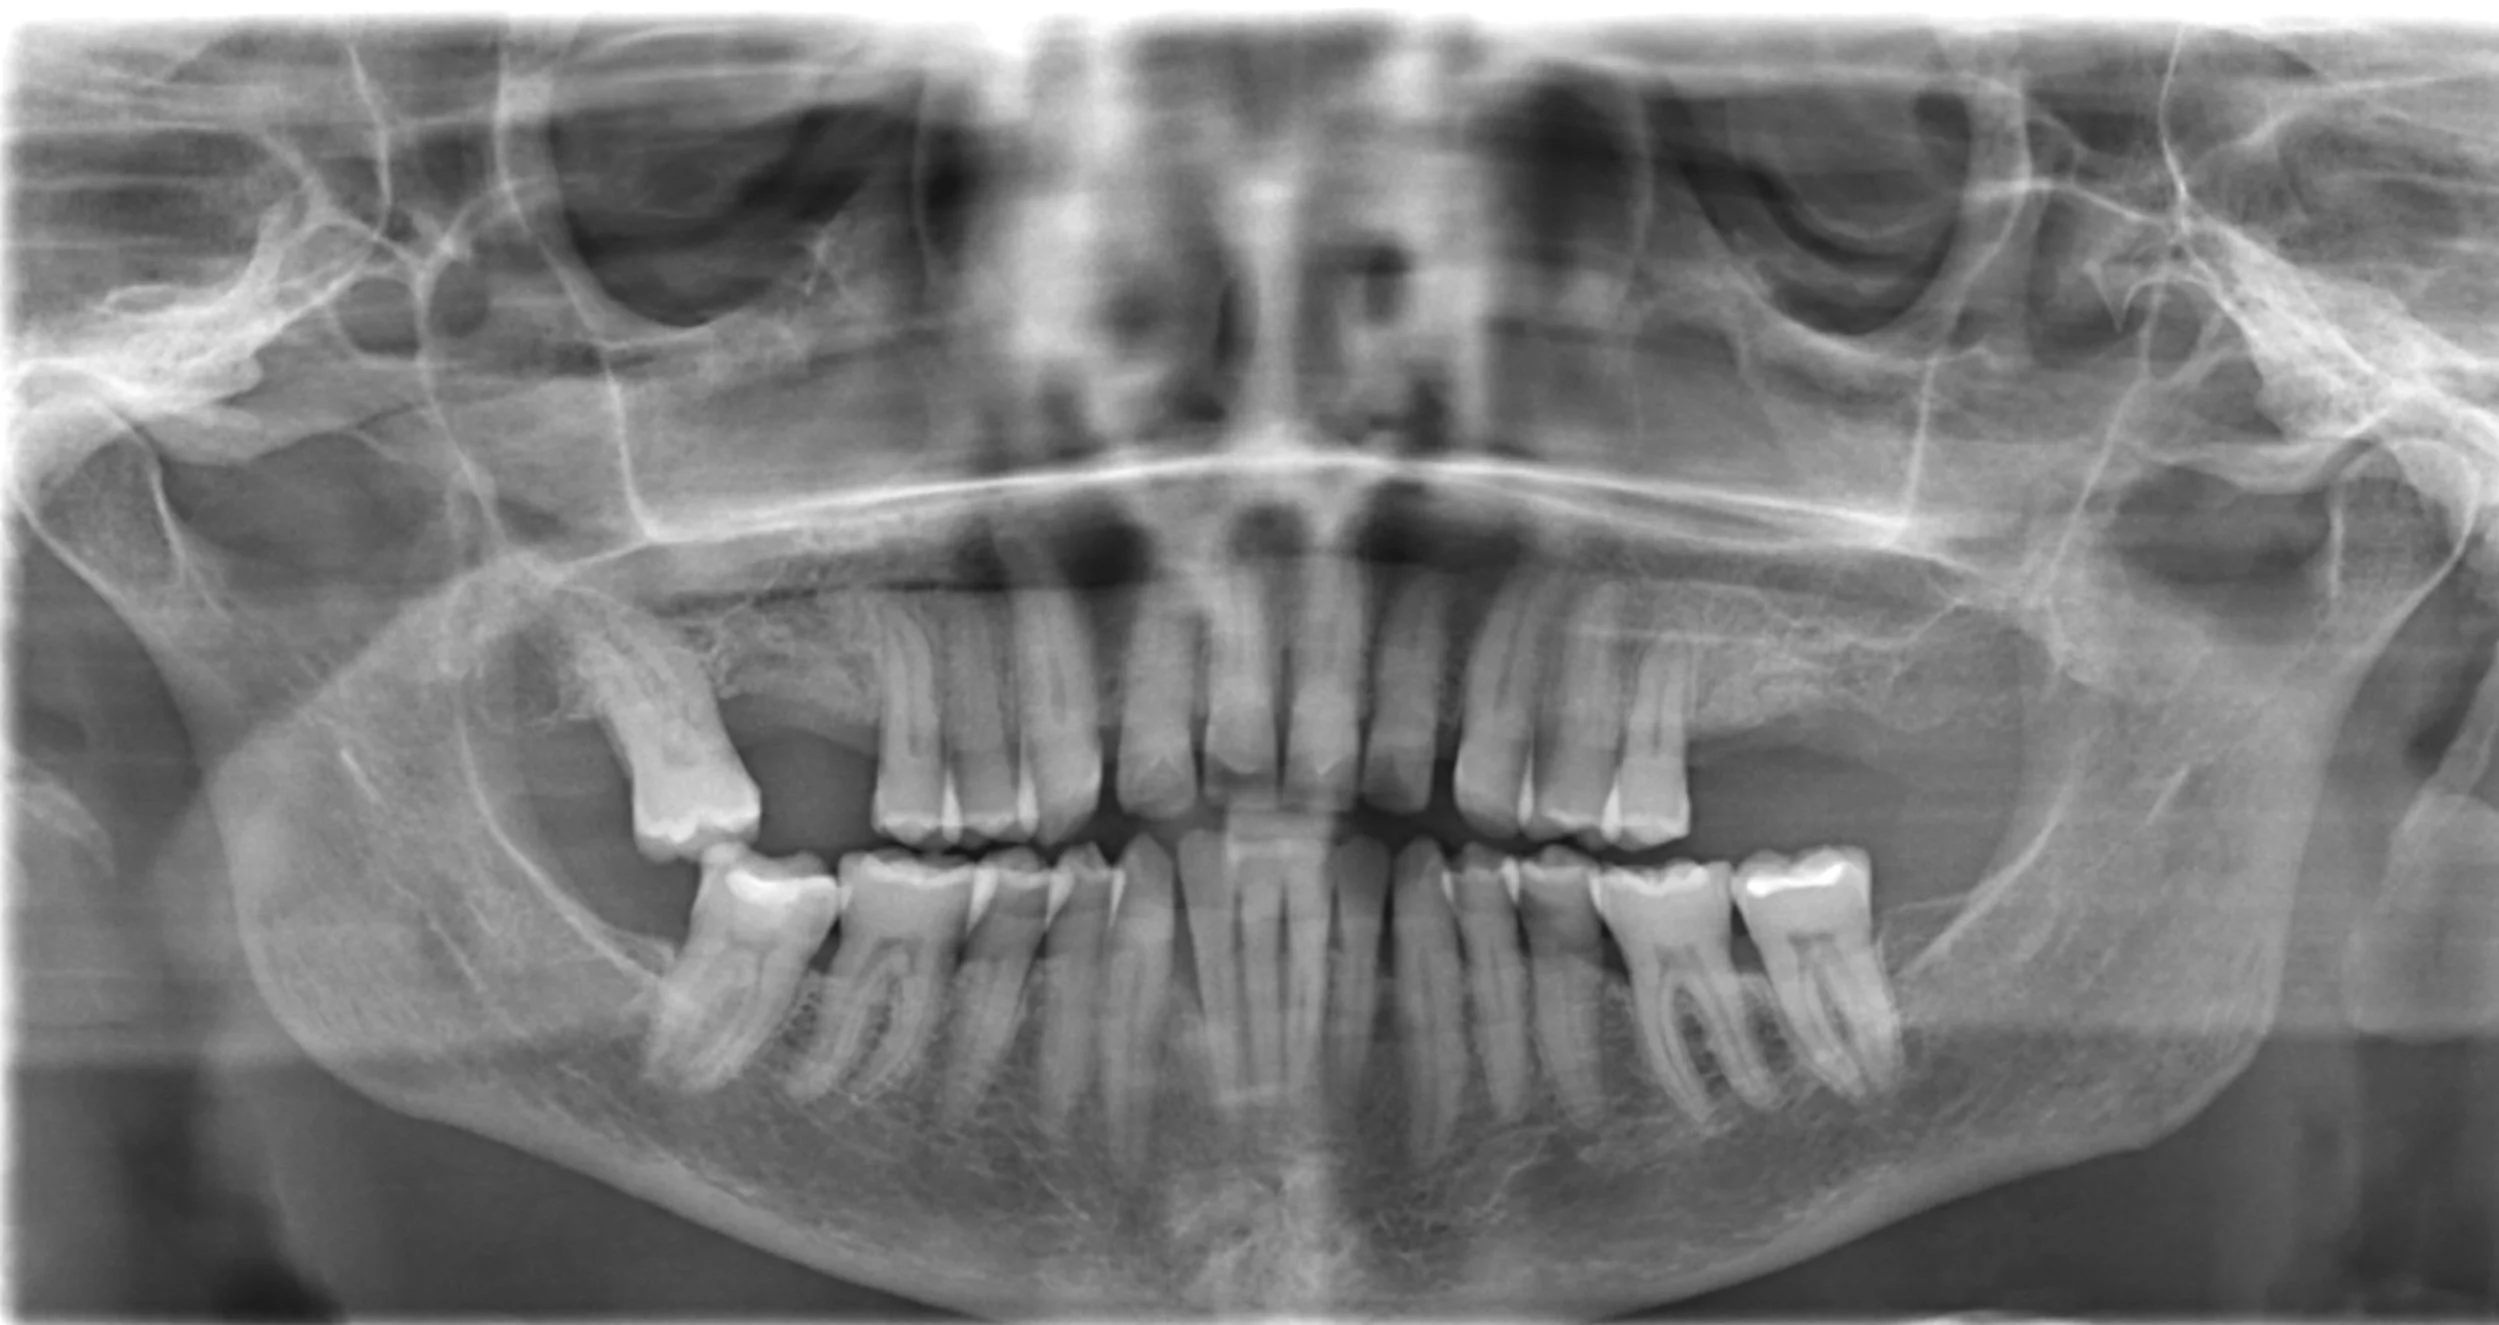

During your initial consultation, we will take a CT scan, a 4D image that allows our specialist to see if you are a fit candidate to receive dental implants. This decision heavily relies on your existing bone level and placement location. This image also defines the size and amount of dental implants to be placed and if any bone graft and membrane will be necessary. In addition, he will use this image to place the implant digitally, allowing visibility to increase predictability and safety prior to surgery. Dr. Ribeiro will work closely with his restorative associates to give you the best path to your new tooth/teeth. Depending on how many teeth you are missing, there are various types of implant-held restorations for your needs.

You are most likely in pain and need to remove a tooth or teeth that no longer have a good prognosis. During your initial consultation, we will take a CT scan, which is a 4D image that allows our specialist to see which teeth need to be extracted and if you are a fit candidate to receive dental implants. This decision heavily relies on your existing bone level, considering the bone you will lose at the time of extraction and the placement location. This image also defines the size and amount of dental implants to be placed.  In addition, he will use this image to place the implant digitally, allowing visibility to increase predictability and safety prior to surgery. Dr. Ribeiro will work closely with his restorative associates to give you the best path forward to your new tooth/teeth. Depending on how many teeth you will need to replace, there are various types of implant held restorations.